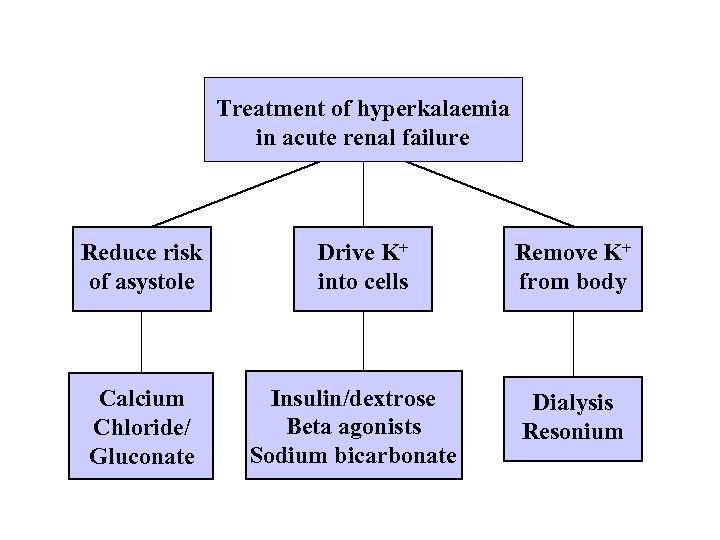

Treatment of hyperkalaemia in acute renal failure Reduce risk of asystole Calcium Chloride/ Gluconate Drive K+ into cells Insulin/dextrose Beta agonists Sodium bicarbonate Remove K+ from body Dialysis Resonium

Treatment of hyperkalaemia in acute renal failure Reduce risk of asystole Calcium Chloride/ Gluconate Drive K+ into cells Insulin/dextrose Beta agonists Sodium bicarbonate Remove K+ from body Dialysis Resonium